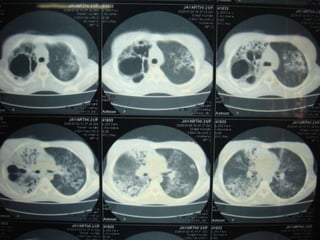

CT Chest: Rt Upper lobe bullous lesion ,Rt middle and lower lobe consolidation with ectatic changes lt upper lobe and lower lobe ECHO: Normal study ,No vegetationsBlood Culture(thrice): Negative for organisms IgM for brucellosis: NegativeTreatment Given: Inj.Cefotaxime,chloroquine,Doxy,Metranidazole,Nebulization, cat-II ATT started

CT Chest: RtUpper lobe bullous lesion ,Rt middle and lower lobe consolidation with ectatic changes lt upper lobe and lower lobe ECHO: Normal study ,No vegetationsBlood Culture(thrice): Negative for organisms IgM for brucellosis: NegativeTreatment Given: Inj.Cefotaxime,chloroquine,Doxy,Metranidazole,Nebulization, cat-II ATT started